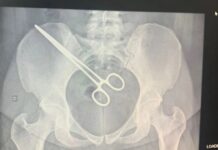

Mulher passa mais de 2 meses com pinça esquecida dentro do corpo após cirurgia

Caso foi descoberto na segunda-feira (12), dois meses depois de ela fazer uma cirurgia para retirada de um feto no hospital de Araçatuba.